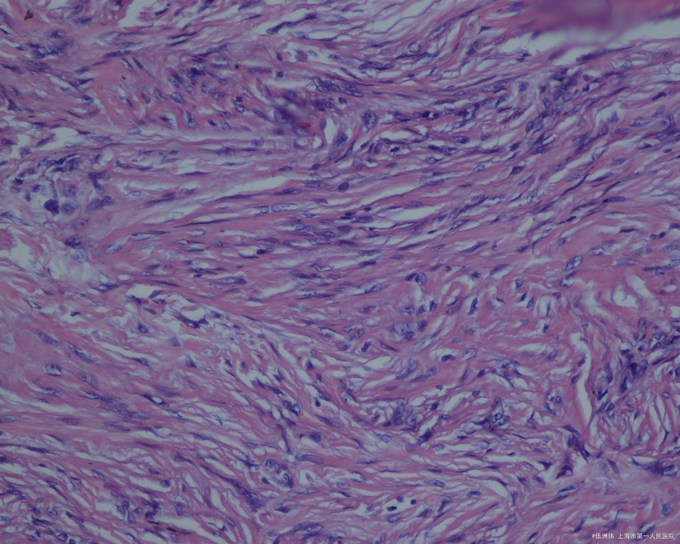

皮损组织病理检查显示结节位于真皮内,无包膜,境界不清,与周围正常组织有明显的交错,下界清楚,上界与表皮之间常夹着一条“境界带”,但瘤组织有时也可与表皮相连。病变组织由成束的成纤维细胞、组织细胞和成熟或幼稚的胶原纤维组织组成,相互交织;病变上方的表皮明显增生,棘层肥厚,皮突延长。偶见有核丝分裂象。

病因 本病的真正病因不明。本病的发生可能是反应性的,与皮肤局部轻微损伤有关,如昆虫叮咬或钝器损伤。亦有人认为与病毒感染也有一定关系。但克隆性分析提示本病是肿瘤性的。 临床表现 多见于四肢伸侧,亦可见于其他部位。皮损表现为圆形或卵圆形丘疹或结节,直径约1cm通常不超过2cm,偶2cm或更大。隆起,坚硬,基底可推动,但与表皮相连。表面的皮肤光滑或粗糙,色泽深浅不一,可为正常肤色,亦可为黄褐色、黑褐色或淡红色。多见于中青年,罕见于儿童,好发于女性。皮损常持久存在,少数可数年后自行消退。通常无自觉症状,偶或有轻度疼痛感。一般为单发,偶或多发。 检查 皮损组织病理检查显示结节位于真皮内,无包膜,境界不清,与周围正常组织有明显的交错,下界清楚,上界与表皮之间常夹着一条“境界带”,但瘤组织有时也可与表皮相连。病变组织由成束的成纤维细胞、组织细胞和成熟或幼稚的胶原纤维组织组成,相互交织;病变上方的表皮明显增生,棘层肥厚,皮突延长。偶见有核丝分裂象。根据肿瘤细胞成分与胶原纤维所占比例分为2种组织类型,即纤维型和细胞型。 诊断 根据临床表现和组织病理检查可以诊断。 1.局部有轻微外伤史。 2.临床表现为皮内丘疹或结节黄褐色或淡红色等,与深部组织不粘连。 3.组织病理检查符合皮肤纤维瘤病理改变。 治疗 一般不需治疗,少数损害数年内可消退。若单个损害有疼痛引起病人痛苦时可行手术切除。皮质类固醇激素皮内注射有一定的疗效。